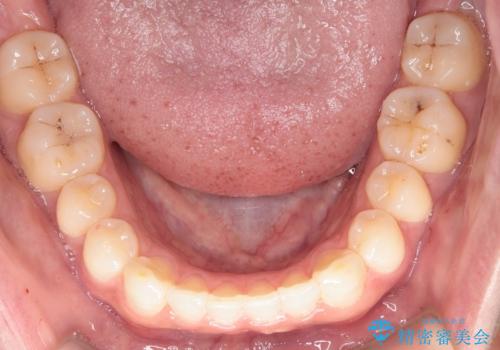

【インビザライン】正中離開を治したい

再矯正ということでがたつきはなくきれいに並んでいましたが、上下のアーチ(歯列弓)の大きさのバランスが悪く、結果的に後戻りの原因になってしまっていました。今回は下のアーチを小さくするためにIPRを行い、かみ合わせのバランスを治しながら前歯の隙間を閉じました。